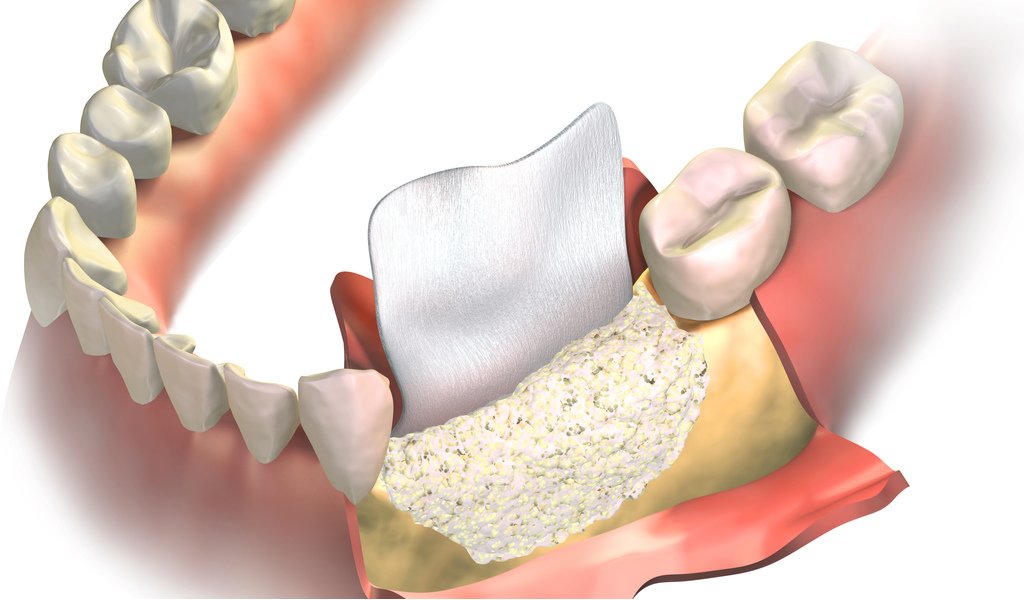

GBR: Rigenerazione Ossea per un Sorriso Rigenerato

La Rigenerazione Ossea è una tecnica chirurgica per aumentare i volumi delle strutture ossee. Questa procedura è fondamentale in casi di atrofia delle creste ossee dovuta all’estrazione di denti o all’edentulia. La tecnica utilizza membrane di diversa natura per promuovere la formazione di nuovo osso, permettendo inserimenti implantari di successo e riabilitazioni protesiche stabili.